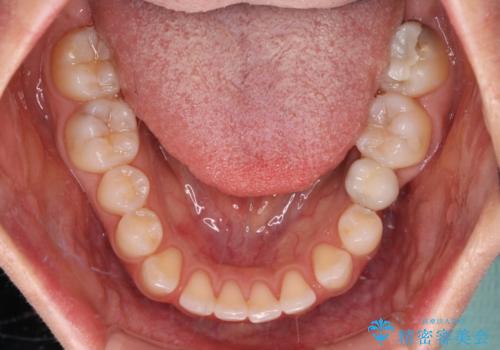

- 大きすぎる上顎前歯と、隙間の空いた下顎歯列を気にして来院された患者様です。

下顎前歯は空隙歯列弓であったので、アンカースクリューとワイヤー装置を用いてスペースを閉じていくこととし、上顎前歯は矯正治療用の仮歯に置き換えた上で、仮歯の大きさを削って小さくしながら、上下前歯部の部分矯正を行うこととしました。